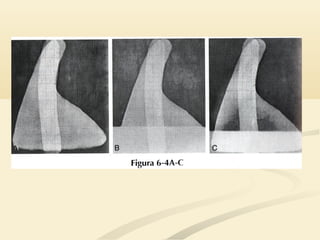

 El LSD ocupa el tórax anterior y medio por encima deEl LSD ocupa el tórax anterior y medio por encima de

la cisura menor.la cisura menor.

 La consolidación del LSD causará un signo de la siluetaLa consolidación del LSD causará un signo de la silueta

en el borde cardíaco derecho superior y en la interfaseen el borde cardíaco derecho superior y en la interfase

 El LSDocupa el tórax anterior y medio por encima deEl LSD ocupa el tórax anterior y medio por encima de la cisura menor.la cisura menor.  La consolidación del LSD causará un signo de la siluetaLa consolidación del LSD causará un signo de la silueta en el borde cardíaco derecho superior y en la interfaseen el borde cardíaco derecho superior y en la interfase traqueopulmonar derecha.traqueopulmonar derecha.

• 20.